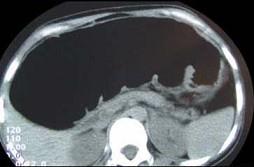

问题 女,30岁,便秘、腹痛腹胀多年,CT检查如图,最可能的诊断是 ( )

选项 A、结肠肠扭转 B、结肠肠栓塞 C、先天性巨结肠 D、结肠肠套叠 E、结肠肠梗阻

答案 C